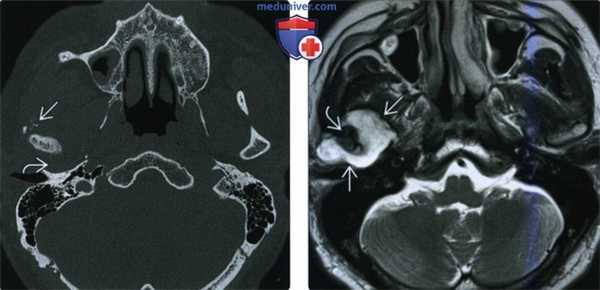

(Слева) КТ с КУ, аксиальная проекция. Злокачественная фиброзная гистиоцитома жевательного пространства и нижней челюсти. Солидная опухоль, которая умеренно накапливает контраст, располагается в правом жевательном пространстве и разрушает нижнюю челюсть, в том числе ее ветвь и тело. Жевательное пространство представляет собой глубокую область лица, в которой может возникать саркома.

(Справа) КТ с КУ, аксиальная проекция, тот же пациент. Солидная опухоль, умеренно накапливающая контраст, разрушает значительную часть нижней челюсти.

(Слева) МРТ Т1ВИ FS с КУ, аксиальная проекция. Лейомиосаркома жевательного пространства высокой степени злокачественности. Опухоль неоднородно накапливает контраст и прорастает в нижнюю челюсть. Только по данным лучевой диагностики дифференцировать различные типы сарком невозможно, за исключением случаев обнаружения матрикса остео- или хондросаркомы.

(Справа) МРТ Т1ВИ FS с КУ, коронарная проекция, тот же пациент. Новообразование, накапливающее контраст, распространяется в полость черепа через овальное отверстие. Отсюда опухоль может прорастать в пещеристый синус.

(Слева) На аксиальной КТ с КУ в жевательном пространстве справа визуализируется злокачественная фиброзная гистиоцитома нижней челюсти в виде минимально контрастирующегося солидного объемного образования, разрушающего ветвь и тело нижней челюсти. Жевательное пространство является известным местом возникновения сарком глубоких областей ли ца.

(Справа) На аксиальной КТ с КУ у этого же пациента визуализируется опухоль в жевательном пространстве справа, приводящая к обширной деструкции нижней челюсти. Обратите внимание на асимметрию лица на стороне поражения.

(Слева) На аксиальной МРТ (Т1 ВИ C+) в жевательном пространстве визуализируется лейомиосаркома высокой степени злокачественности, неравномерно накапливающая контраст и поражающая нижнюю челюсть. Большинство типов сарком жевательного пространства сложно дифференцировать в отсутствие костного или хондроидного матрикса.

(Справа) На корональной МРТ (Т1 ВИ С+ FS) у этого же пациента визуализируется контрастирующаяся опухоль с интракраниальным распространением через овальное отверстие а и поражением кавернозного синуса.